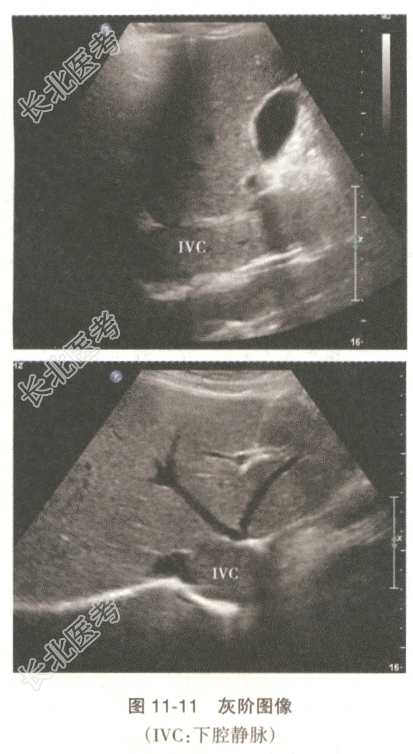

患者,女性,48岁。子宫肌瘤剔除术后复发,1个月前入院术前检查发现心脏占位。下腔静脉的声像图表现如图11-11。

- 多项选择题1.为明确诊断,下一步应进行的超声检查为

D、观察下腔静脉内病变的范围

H、下腔静脉CDFI成像

I、观察下腔静脉内病变与心脏占位之间的关系